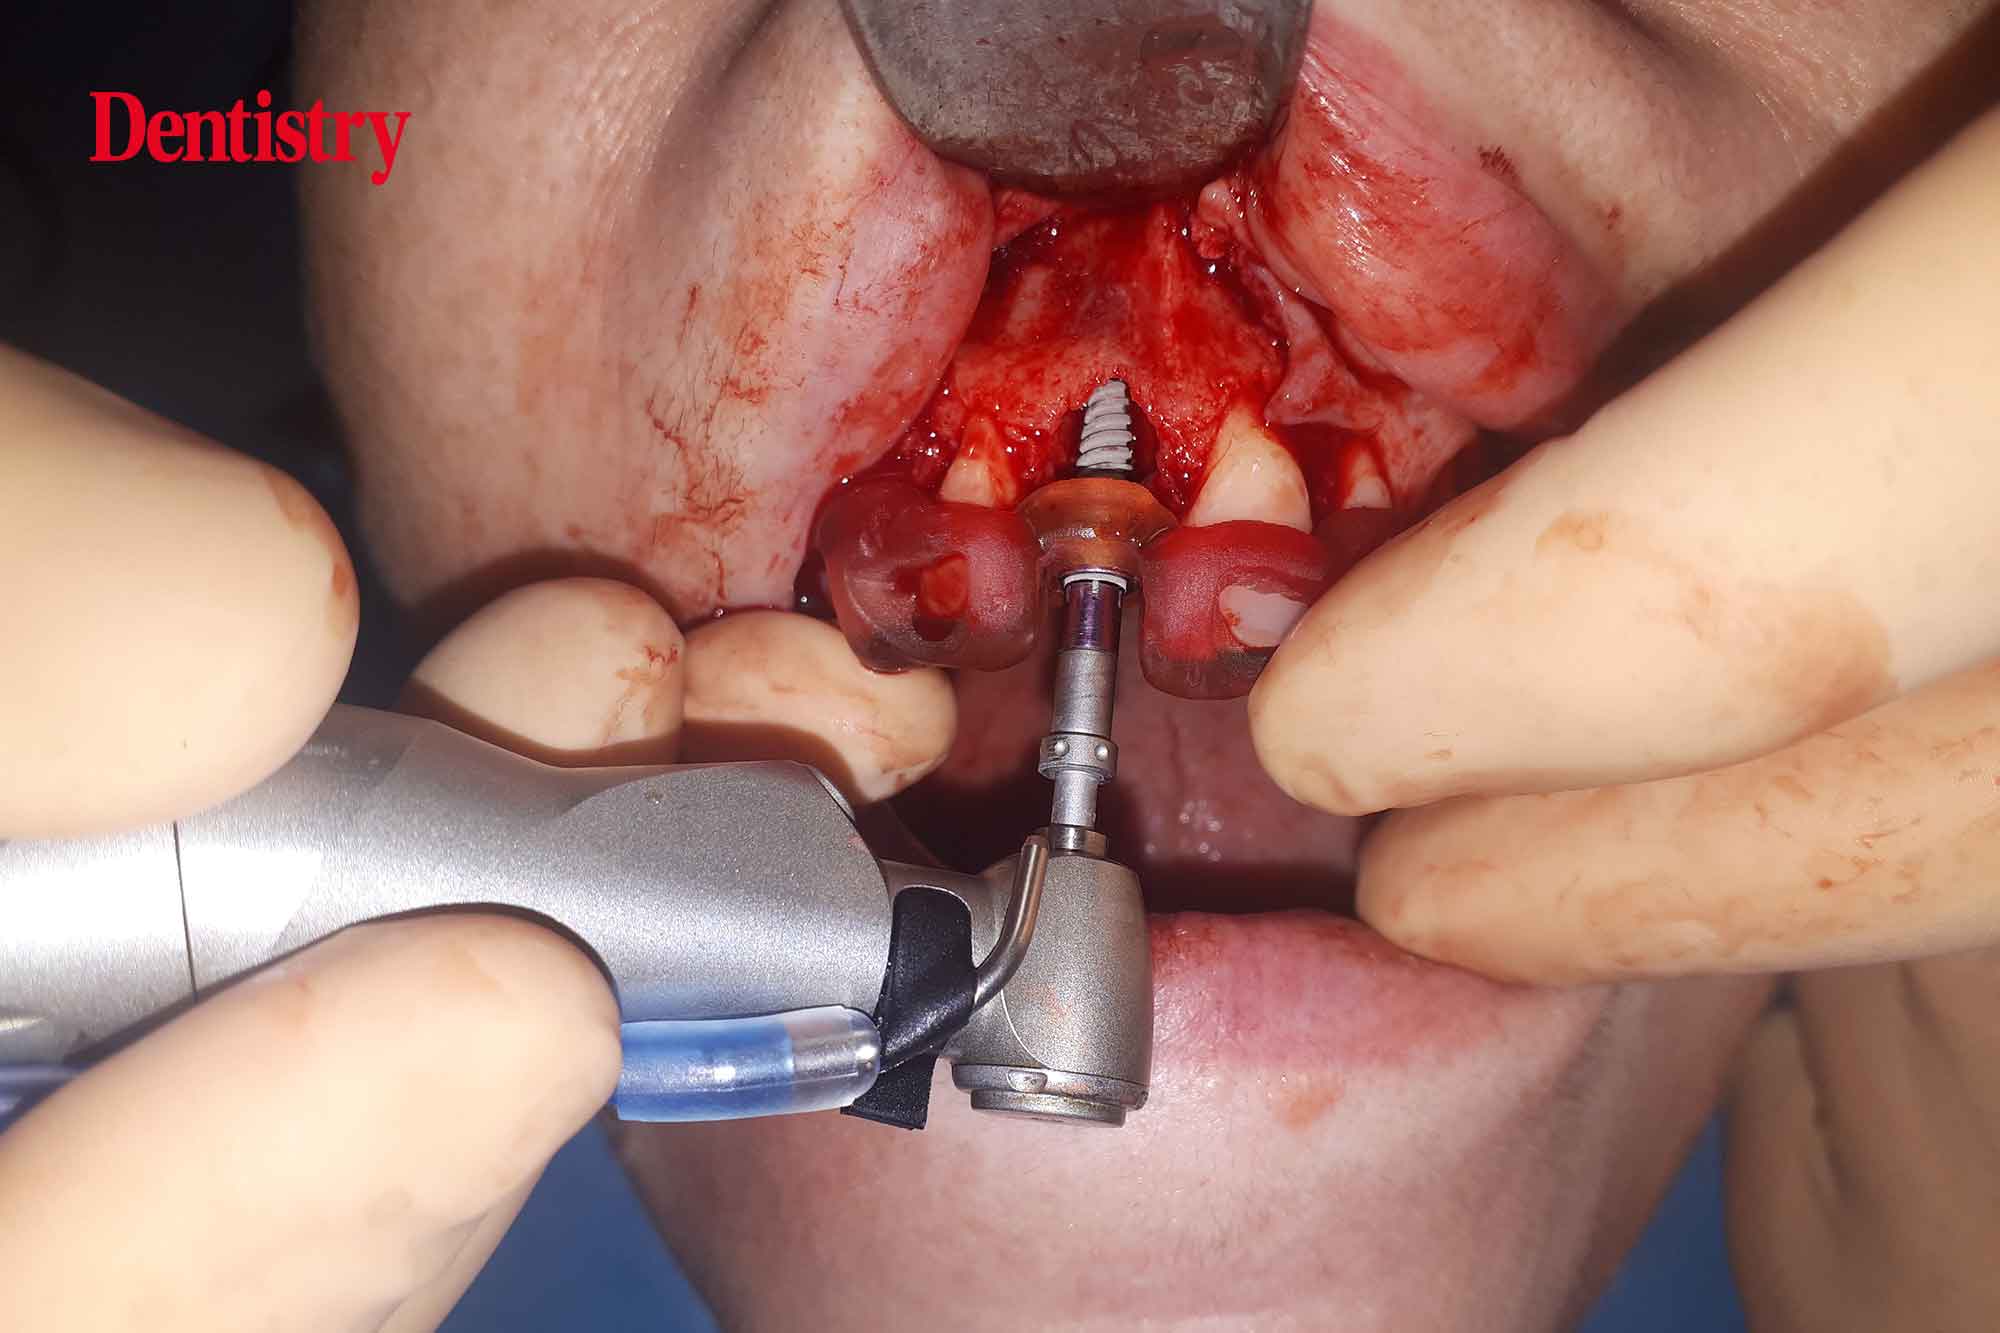

Next, an osteotomy was prepared to the predetermined length, ensuring no lateral movements. The guide had been designed to engage both palatally and apically to the root socket.

Next, the implant was inserted to 45Ncm torque, again confirming good primary stability and insertion torque. This is key had the patient wished to have the tooth immediately restored with a temporary crown.